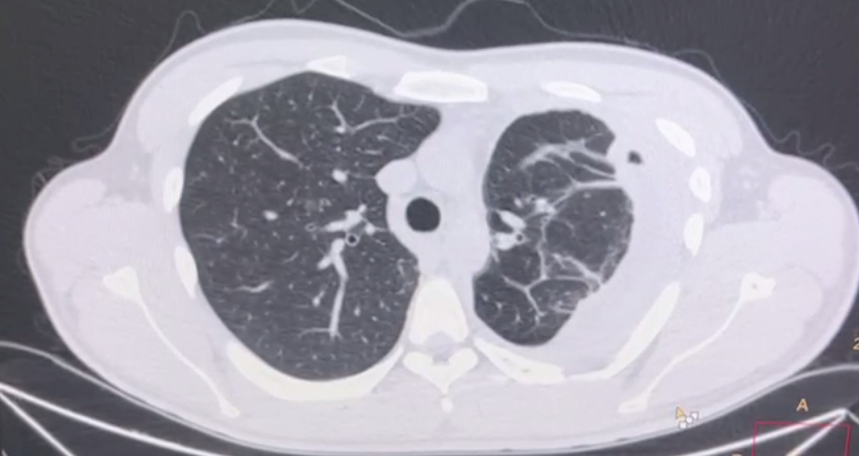

draurtecho Jul 17, 2024 tuberculosis pleural y pulmonar La tuberculosis puede presentarse de muchas formas y dar síntomas clínicos como fiebre tos, pérdida de peso. Una de las presentaciones más frecuente a nivel pleural es el derrame pleural y a nivel pulmonar podría presentarse en forma de nódulos, como se muestra en las siguientes imágenes. No Comments InNeumología